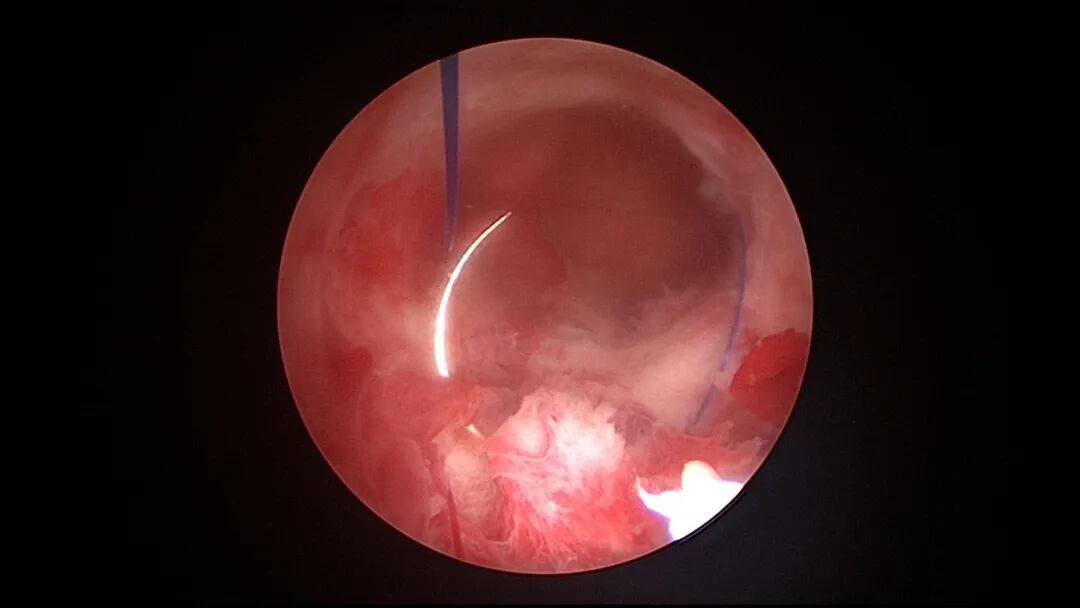

取胚术后宫壁缝合1针宫颈缝扎固定节育环图片及视频

取胚术后宫壁缝合2针线圈固定节育环图片及视频

宫腔镜下节育环缝合固定注意事项:腺肌症子宫、终止妊娠后子宫,子宫长径大于7cm者,或盆腔粘连、膀胱充盈牵拉子宫者,宫深可能超过12cm,宫腔很大,尤其是肥胖病人,宫腔镜器械长度无法到达宫底,缝合很困难,可能无法看到宫腔后壁,甚至找不到附着在宫腔后壁的缝针,偶有放弃缝合固定病例,待药物治疗、子宫复旧及器械充分准备后择期再做固定。终止妊娠后子宫敏感,收缩放松频率快,在放松时间段无法完成缝合操作时,手术时间可能延长,因此清除胚胎后不要急着用缩宫素,否则影响缝合操作。取胚或内膜吸刮后宫腔有出血,视野不清,缝合比较困难,调高膨宫压会有改善。4-0线很细,很难在同一个部位打方结,打单结即可,肌层对单结的卡压足够固定节育环,甚至不需要肌层卡压固定结,仅仅一个限位结就足够固定节育环(体外打结很容易,多打几个结也无妨)。三种简化方案核心都是避免推结,费时费力,可能推结不到位,或过度牵拉撕裂组织,导致固定失败。可以根据病人具体情况及医生擅长选择一种简化方案固定,也可以几种简化方案联合使用。